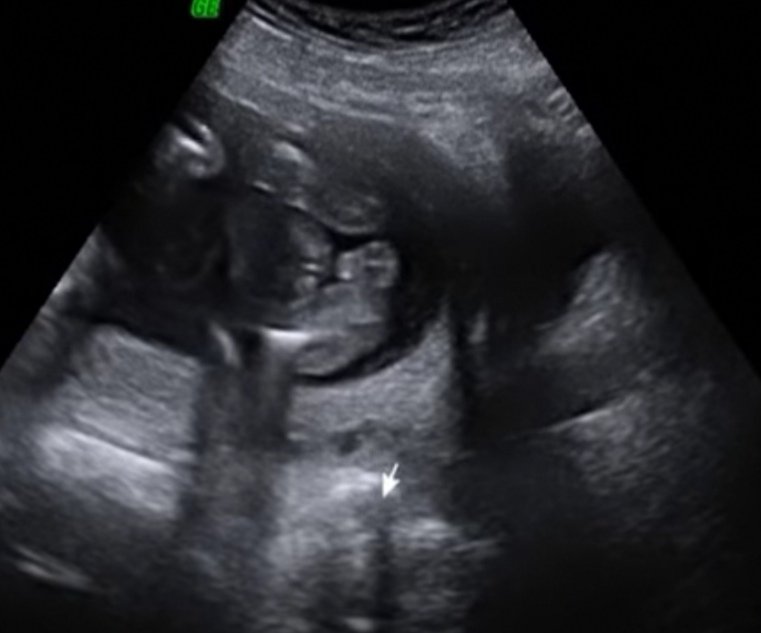

Dziewczyny mała zagadka. Jaka to płeć? Zobacz załącznik 880730

No mi jeden powiedział tak, a drugi inaczej... Któryś się pomylił...Cieżko dojrzeć w ogóle kształt dziecka [emoji2]

Mi lekarze na obu prenatalnych określali płeć na podstawie wyrostka.

Wierzę, że wiedzą co robią. Tym bardziej, że z dwóch rożnych miast lekarze.